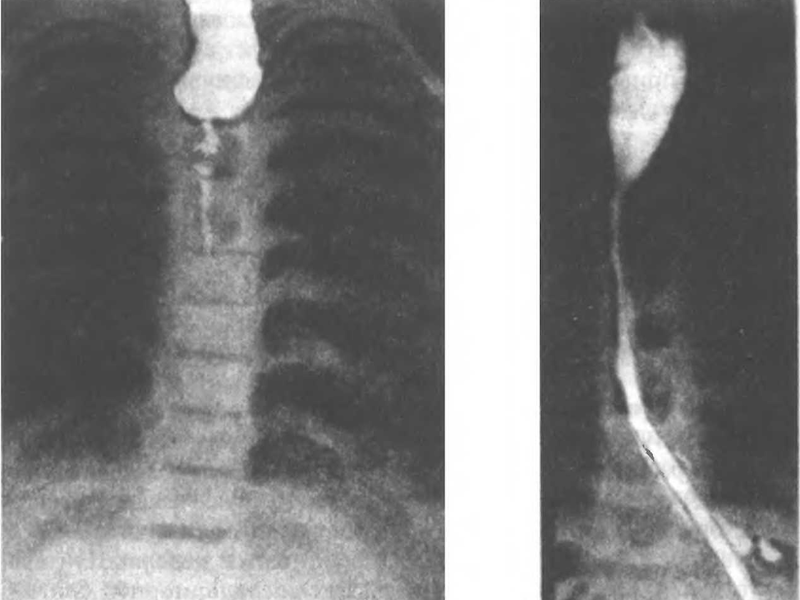

В случае, если эндоскопия невозможна из-за отсутствия оборудования или крайней степени сужения пищевода, для диагностики непроходимости применяют рентгенографию. Пациенту дают выпить смесь, содержащую соли бария, непроницаемые для рентгеновских лучей. После этого делают серию снимков, позволяющих оценить уровень и распространенность сужения пищевода, а также моторику его стенок.